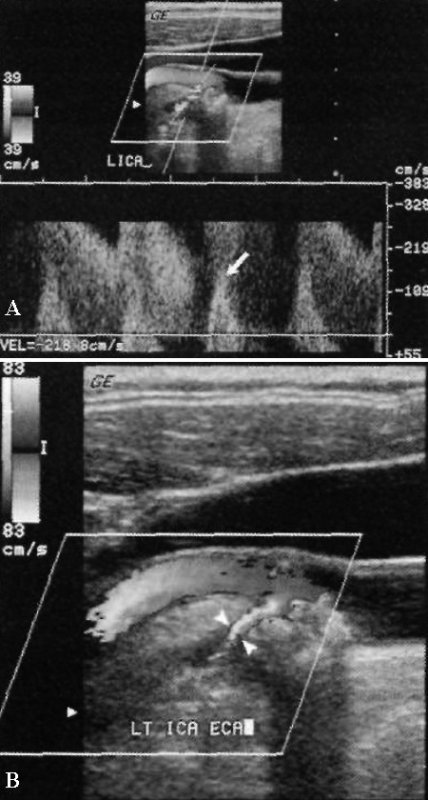

УЗИ: Тяжелый стеноз внутренней сонной артерии на уровне бифуркации

Фото 5. Тяжелый стеноз внутренней сонной артерии на уровне бифуркации. А – значительное увеличение максимальной скорости кровотока > 380 м/с. Наблюдается эффект смешивания: стрелкой обозначен систолический пик, который закручивается и смещается ниже изолинии. Курсором отмечен показатель увеличенной конечно-диастолической скорости до 218 см/с. Скорость потока в общей сонной артерии составляет 50 см/см, соответственно, значение отношения скоростей внутренней и общей сонных артерий составляет 7,6, что свидетельствует о стенозе очень высокой степени (80-99%). В – цветовая допплерограмма того же больного: указателями отмечено выраженное сужение внутренней сонной артерии атеросклеротической бляшкой